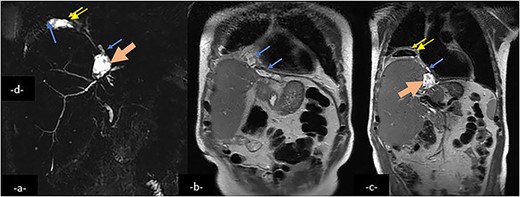

Magnetic resonance cholangio pancreatography (MRCP) in Radial T2 SSFSE sequence and coronal T2 showing a collection (large arrow) in the left hepatic lobe, subphrenic collection (arrow) and right pleural collection (double arrow) containing air and communicating with airways.